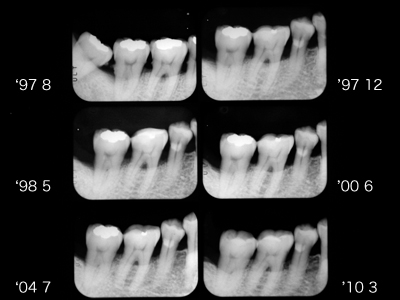

'97初診当時40歳男性。右下6に頬舌側から2度の根分岐部病変が存在。スケーリング、ルートプレーニング、FOPを経て6ヶ月毎のメインテナンスが14年継続しています。

挺出によって垂直ポケットが減少すれば水平ポケットはメインテナンスできるのです。歯間乳頭部にはクリーピングもみられます。

x線写真でも安定しています。